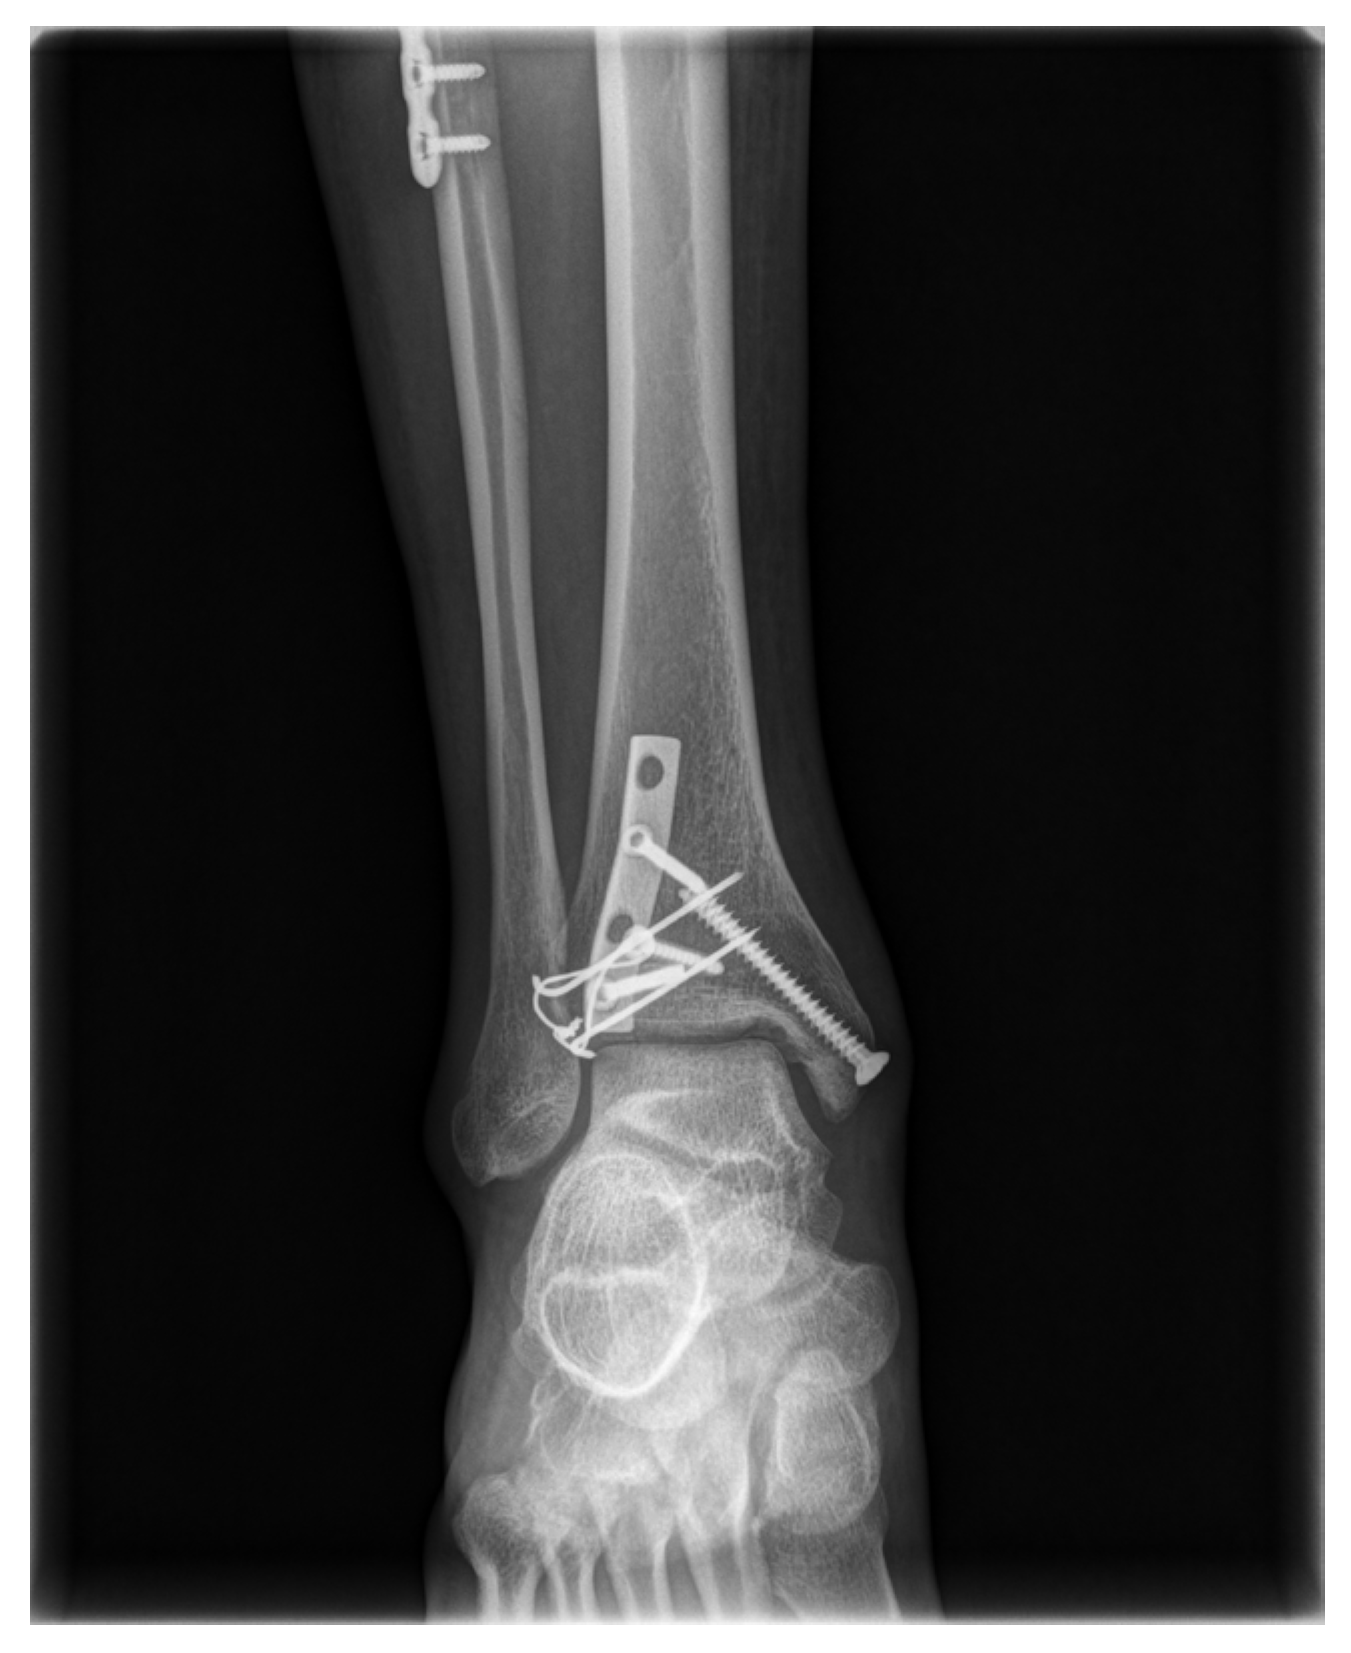

A Tension-Band Wiring Technique for Direct Fixation of a Chaput Tubercle Fracture: Technical Note

2. Surgical Technique